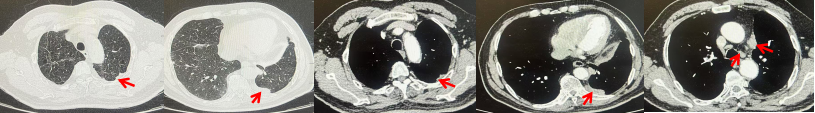

71岁男性,高血压病史20年,口服药物治疗,无糖尿病、心脏病等基础疾病,吸烟史50年,20支/天,已戒1年余,无饮酒史,无肿瘤家族史。2023.11因咳嗽、咳痰行胸CT检查:左肺下叶占位性病变,大小约12mmx8mm(如图5)。2023.11.20行“单孔胸腔镜左肺中下叶切除、肺门及纵隔淋巴结清扫、胸膜粘连松解术”;术后病理:(左肺下叶)结合免疫组化鳞状细胞癌(中、低分化),局部见脉管内癌栓,未见确切神经侵犯,(气管切缘)净。(淋巴结)未见转移癌0/19(4组0/1;5组0/1;6组0/2;7组0/1;9组0/1;10组0/2;11组0/3;12组0/2;13组0/2;14组0/4)。术后分期pT1bN0M0 IA期,术后定期复查。

2024.09.12复查胸部CT示左侧胸膜结节,大者约为27mmx13mm,考虑转移可能性大,纵隔淋巴结增大,恶性?(如图6)。患者行胸膜穿刺活检取病理,结果示(胸膜)结合免疫组化,支持鳞状细胞癌,PD-L1(克隆号28-8)TPS约20%。分期为rT0N2bM1a IVA期,DFS为10个月。2024.09.24起行替雷利珠单抗联合紫杉醇+卡铂方案治疗4周期,复查胸CT评效SD(如图7)。后患者因脑梗塞停止治疗,于综合医院就诊,后未返院复查及治疗。

图5:患者手术前(2023.11)胸部CT肺窗及纵隔窗

图6:患者胸膜及纵隔转移(2024.09)胸部CT肺窗及纵隔窗